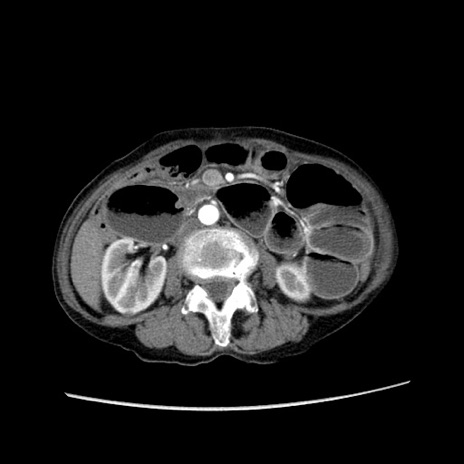

症例25(横断像)

【症例】80歳代女性

【主訴】胸のつかえ感

【現病歴】約9時間前に食後から胸のつかえた感じあり、嘔吐あり、来院。

【既往歴】胃癌(全摘)、胆摘、虫垂炎

【身体所見】心窩部に圧痛あり、反跳痛なし。

【データ】WBC 5700、CRP 0.05